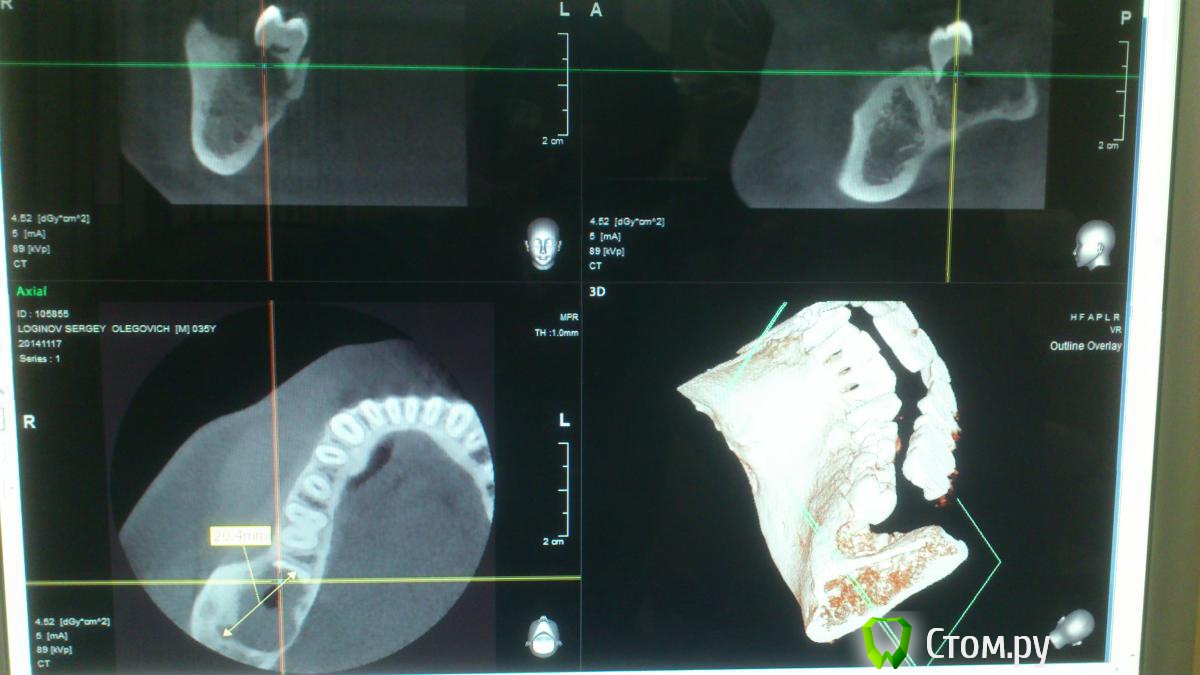

Larnary Опубликовано 17 ноября, 2014 Поделиться Опубликовано 17 ноября, 2014 (изменено) Пришёл на консутацию пациент с КТ. Вижу крупное кистозное образовамие в области 47 и отсутствующего 48.Со слов пациента 48 не было никогда. Отмечаетя полная резорбция корней 47. Сделал принтскрин и направил к онкологу.Пациент обещал позвонить и сообщить результаты Изменено 17 ноября, 2014 пользователем Larnary Ссылка на комментарий

Larnary Опубликовано 17 ноября, 2014 Автор Поделиться Опубликовано 17 ноября, 2014 Да.потпу и направил к онкологу,тк. сильнейшая резорбция корней. думаю круто для кисты. но и полость кисты однородна по структуре Ссылка на комментарий

PLAY Опубликовано 17 ноября, 2014 Поделиться Опубликовано 17 ноября, 2014 А с чего вы взяли, что они резорбированы? Срез сделан неправильно, имхо. Орто надо. я вижу на 2х срезах предоставленной кт-резорбцию корней. фолликулярная киста проходит через эмалево-цементную границу, тут образование, просто отхапало пол-зуба, линия новообразования неравномерная, меня бы это насторожило Ссылка на комментарий

Larnary Опубликовано 17 ноября, 2014 Автор Поделиться Опубликовано 17 ноября, 2014 врачи потому и направили на КТ,тк на панораме нет корней.только краешек медиального корня. да и я кт вертел. нет их там Ссылка на комментарий

Larnary Опубликовано 17 ноября, 2014 Автор Поделиться Опубликовано 17 ноября, 2014 увеличил нижний кадр Ссылка на комментарий